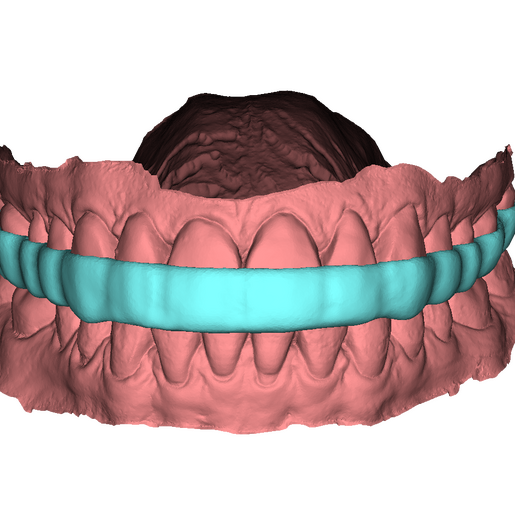

DSD Bite Splint Design

The DSD Bite Splint (night guard) is designed to be worn after a full mouth rehabilitation to protect DSD Natural Restorations and/or DSD Direct composite restorations. The splint design can be used for both milling and printing.

This product is ideal when you need to protect restorations that have already been placed to help avoid possible fractures due to grinding and bruxism.

An .STL file of the DSD Bite Splint design that can be used for manufacture, either by DSD Lab or your local lab.